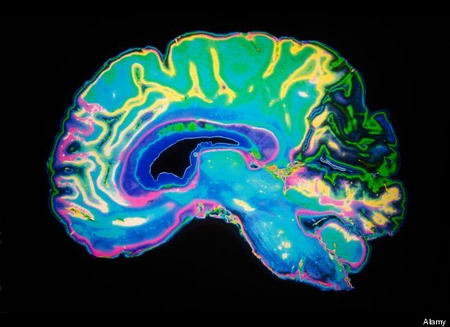

Trong nghiên cứu này, các nhà khoa học sử dụng 2 phương pháp: nghiên cứu hành vi và hình ảnh học thần kinh để xác định tác động của việc học ngoại ngữ tới sự nhận thức ở người lớn.

Theo các nhà khoa học, do mạng lưới kiểm soát chức năng trong não bộ phải xử lý hai loại ngôn ngữ, chức năng của vùng não bộ kiểm soát khả năng tập trung và nhận thức cũng nhờ đó mà được tăng cường. Dần dần, quá trình này làm tăng năng lực thích nghi của trí não.

Ngoài ra, việc sử dụng 2 ngôn ngữ còn giúp cải thiện khả năng dự trữ nhận thức trong não, kích thích những hoạt động trí tuệ và thể chất khi về già.

“Kinh nghiệm lâu dài trong việc sử dụng 2 ngôn ngữ sẽ tái tổ chức mạng nơ-ron trong não bộ, tạo nền tảng tích cực cho quá trình kiểm soát và duy trì năng lực nhận thức về sau”, tiến sĩ Ellen Bialystok, trưởng nhóm nghiên cứu nhận định.